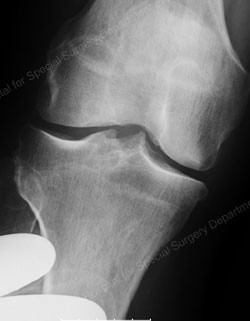

Figure: Medial compartment osteoarthritis

The knee is made up of three compartments: the medial compartment (located on the inside of the knee), the lateral compartment (located on the outside of the knee), and the patellofemoral compartment (located in the front of the knee). In a particular group of osteoarthritis patients, however, the entire knee is not affected by the arthritis. In some patients, only the medial compartment (or, less commonly, only the lateral compartment) may be affected by the disease. For those patients, unicondylar (partial) knee replacement can be considered a treatment option. The term “unicondylar” refers to the replacement of only one section of the smooth bone ends (condyles) – the medial or lateral compartment – as compared to total knee replacement, which involves replacement of all three compartments.